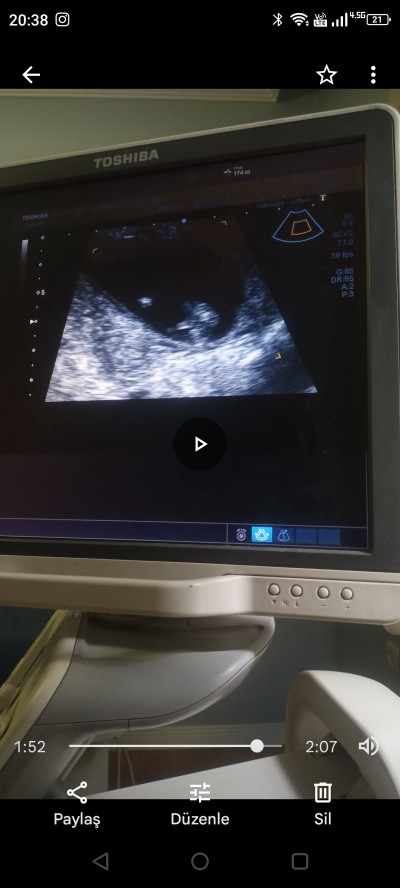

Kizlar ultrasonda cinsiyet görebiliyor musunuz? Görselde bacak arası var ama secemedim ben tesekkurler<3

Gebelik haftası 14